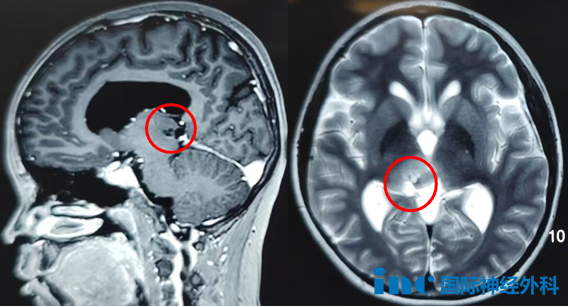

12岁女孩诺诺出现突发性头晕、呕吐及食欲减退症状,影像学检查发现左侧丘脑占位性病变,大小约37mm×45mm×40mm,第三脑室受压,双侧脑室增宽。面对这一诊断结果,诺诺父母犹如遭受晴天霹雳,迫切希望立即手术解除病痛。然而,当肿瘤位于大脑深部且体积巨大时,治疗决策变得尤为艰难。

今年8月,13岁男孩新城接受巴教授主刀的手术治疗。手术过程让参与医生深感技术难度:肿瘤位于丘脑-中脑这一复杂区域,手术路径狭长,操作空间有限,且周围布满重要神经血管;肿瘤边界不清,正常脑组织与病变区域呈浸润性生长,对手术精度要求极高;脉络膜后内侧动脉被肿瘤完全包绕,重要血管穿行其中。术后第一天患者即恢复活力,第三天已能独立行走。